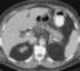

Adjacent abscess

An abscess is a collection of pus that has built up within the tissue of the body. Signs and symptoms of abscesses include redness, pain, warmth, and swelling. [Source: Wikipedia ]